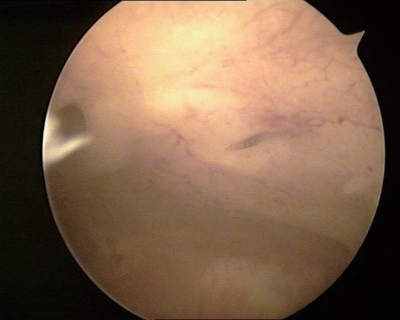

③分泌期子宫内膜:内膜往往呈半球状或息肉样突起,水肿样改变,半透明白色或黄白色,可清晰透见毛细血管网,皱褶减少变浅,腺体开口难辨(图3-7)。